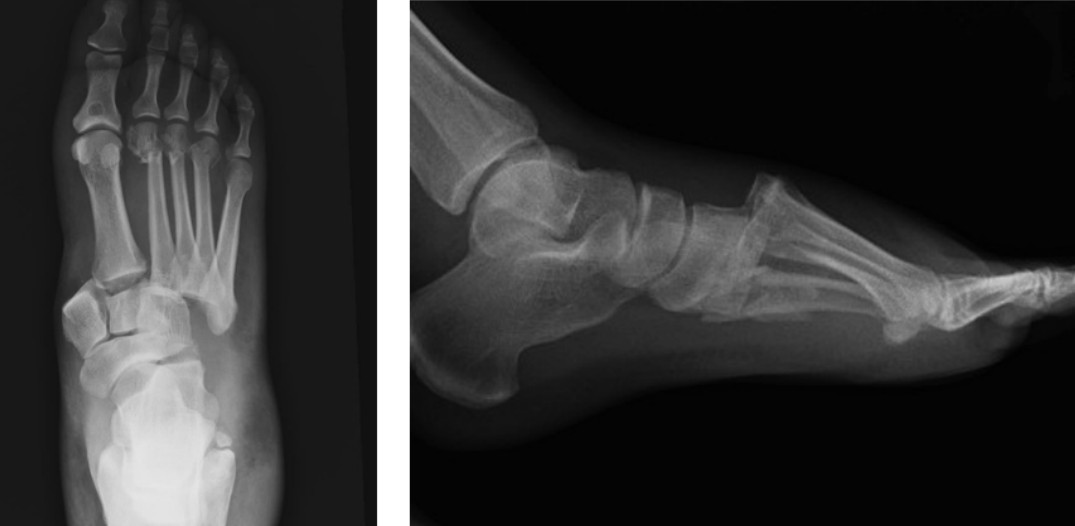

Foot injury

A 20-year-old female is brought in by ambulance after a dirt bike accident. She has a painful and swollen right …